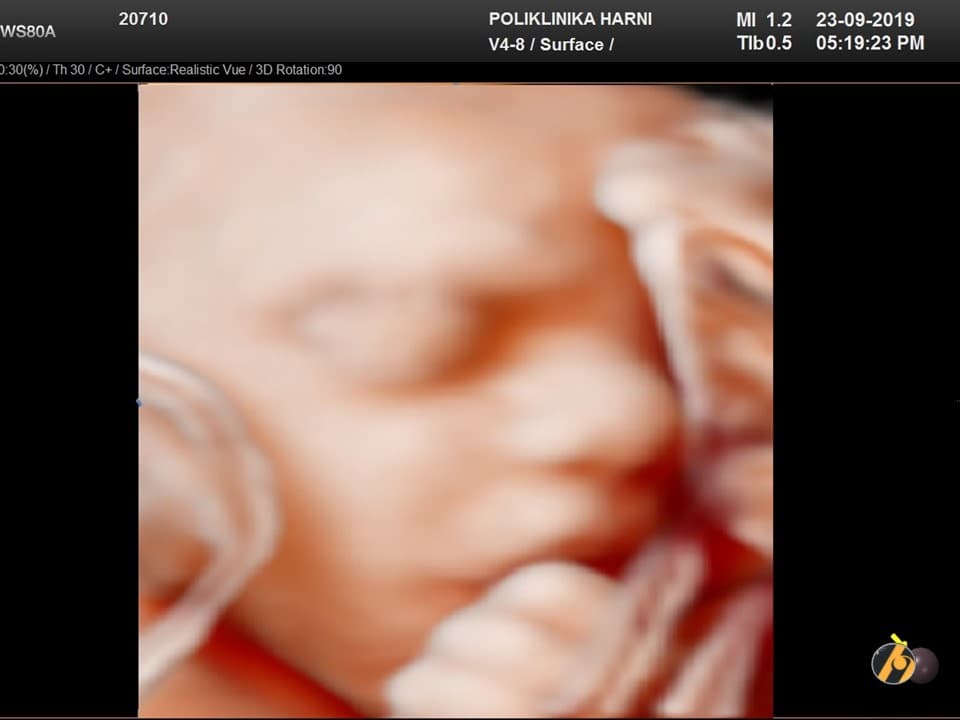

U ovo vrijeme beba osjeća svoju okolinu, kao i pupčanu vrpcu. Fetoskopski snimci pokazuju kako se beba zna igrati s pupčanom vrpcom i opnom koja ih okružuje / fetal grasping. U jednom slučaju može ručicama loviti pupčanu vrpcu, u drugome svoje lice ili ručice trljati o opnu koja ju okružuje.